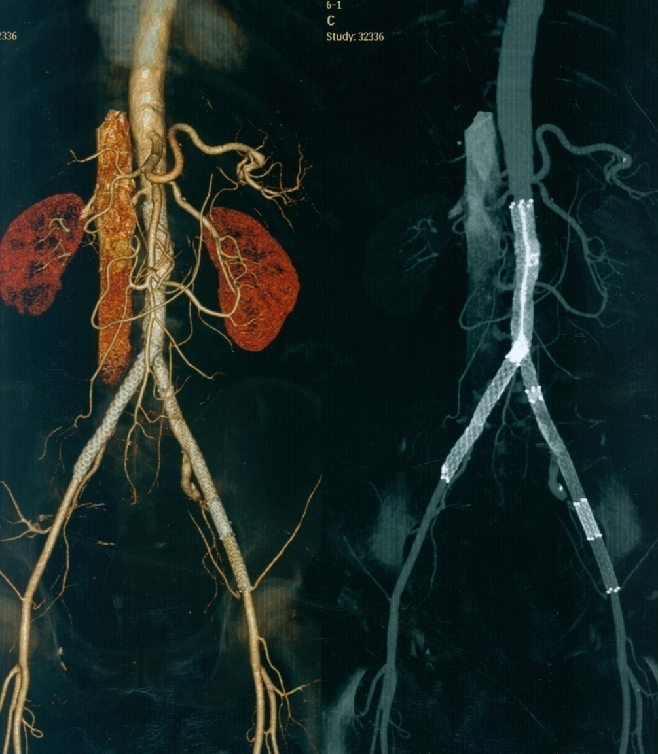

病例3

女性、61岁,病史:右下肢无力三个月

预置导管溶栓3天后效果明显

预置导管溶栓7天后效果满意并行支架术